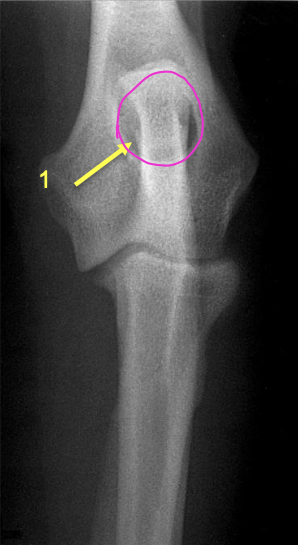

what is 11?

lateral epicondyle

what is 12?

medial epicondyle

what are the white arrowheads pointing to?

lateral supracondylar crest

what is the black arrowhead pointing to?

caudal aspect of the lateral epicondyle

what is the red circle highlighting?

tricipital line present in the humerus

what is the orange circle highlighting?

deltoid tuberosity

where does the tricipital line of the humerus extend?

disto-cranially to merge with the deltoid tuberosity